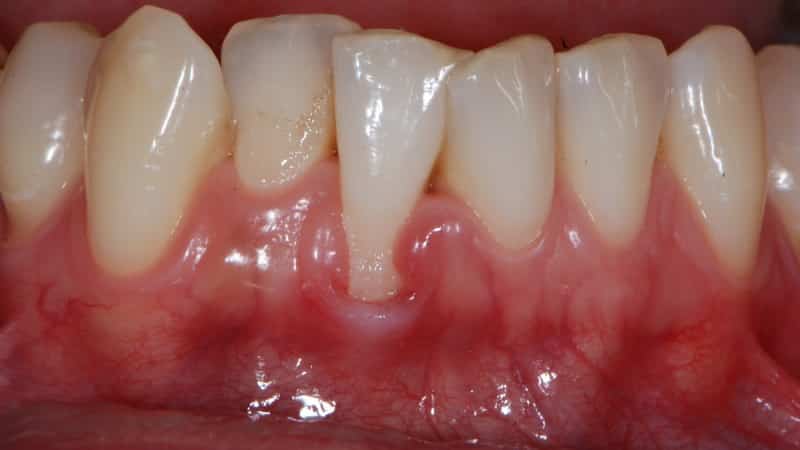

Рецессия десен – это состояние, при котором корни зубов становятся видимыми, что вызывает как физический, так и психологический дискомфорт у пациента. Это заболевание может начаться с одного зуба и постепенно затрагивать другие, причем нижняя челюсть страдает от него значительно чаще, чем верхняя.

Устранение рецессии десны на имплантате или здоровом зубе возможно после определения стадии заболевания и основных симптомов.

- полное или частичное обнажение корня зуба;

- заметное снижение уровня десны;